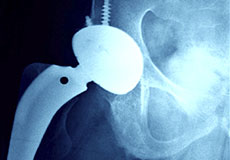

Radiography ("x-ray") tuned for sports and joint imaging and performed on high quality equipment by meticulous technologists with specialized training in the types of imaging we perform. These technologists regularly participate in collaborative imaging review with the radiologists to ensure the highest standard of care.